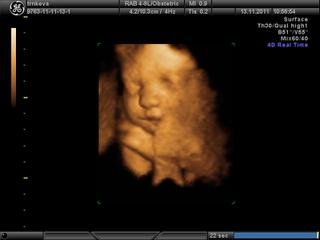

tak babule dnes nám 4D vyšlo na 100% a meno už máme dávno vybraté NINA